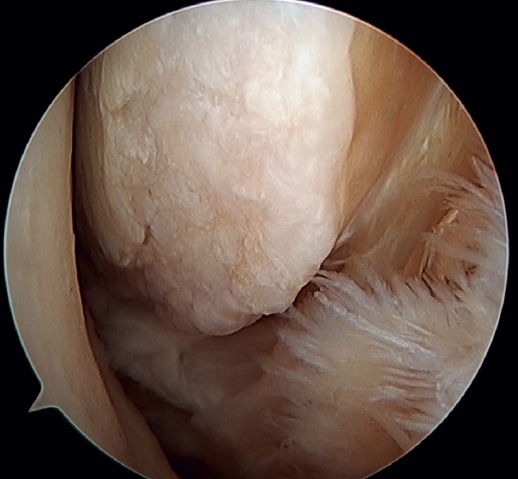

A recent consensus(64) recommends reconstruction of the ATFL and CFL (Figures 5 and 6) in cases of generalized laxity or when there is poor tissue quality. Other indications would be when there are doubts about subtalar stability or in patients with a ruptured CFL. For some authors, BMI > 30 kg/m2 would also be an indication for this technique.

In 2022, Ferkel(30) published the indications for reconstruction: failure of ligament repair, BMI > 30 kg/m2, cases of generalized laxity, athletes or workers with a high functional demand, and cases where poor tissue quality is observed intraoperatively. Another indication is when there is significant instability with a talar tilt angle difference of over 10° with respect to the contralateral ankle, or an absolute angle of more than15°. In the same paper, this author concluded that direct arthroscopic repair of the ATFL is an excellent technique in selected cases.